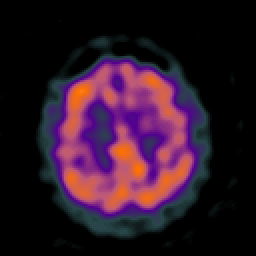

Huntington's Chorea, MR -- Slice #15

[Home][Help][Clinical] Slice 15